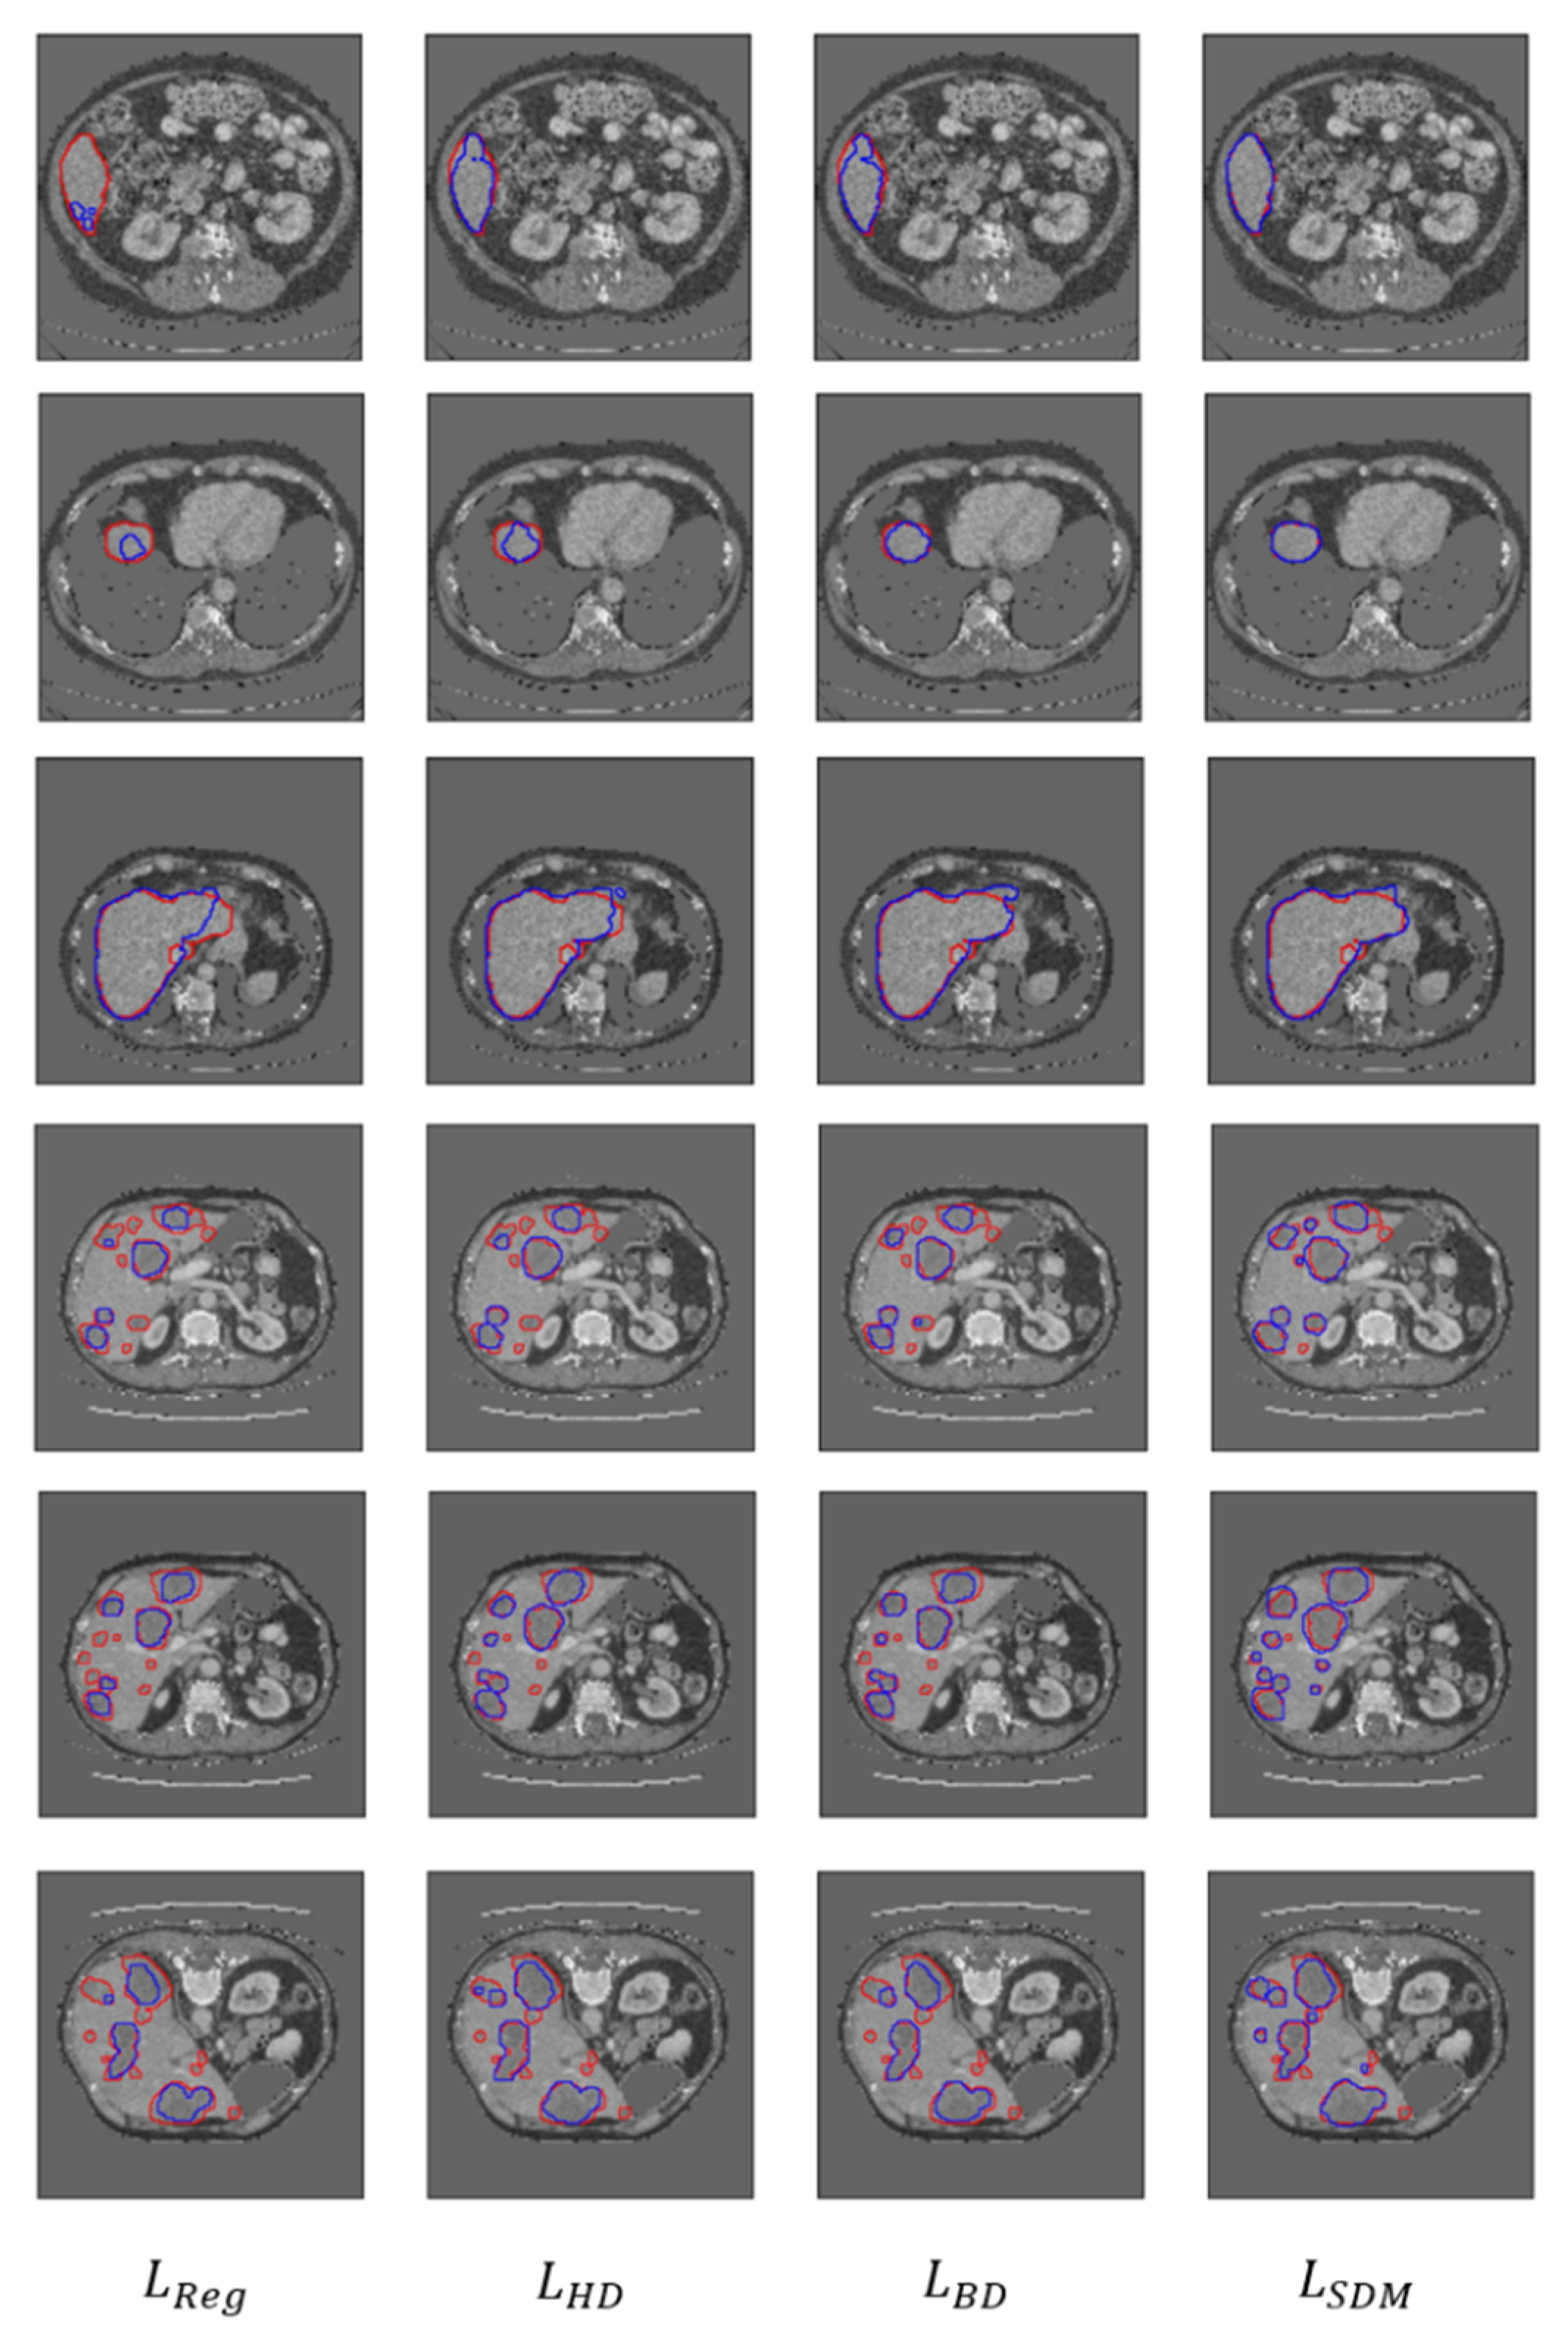

3.2.2. Qualitative Evaluation